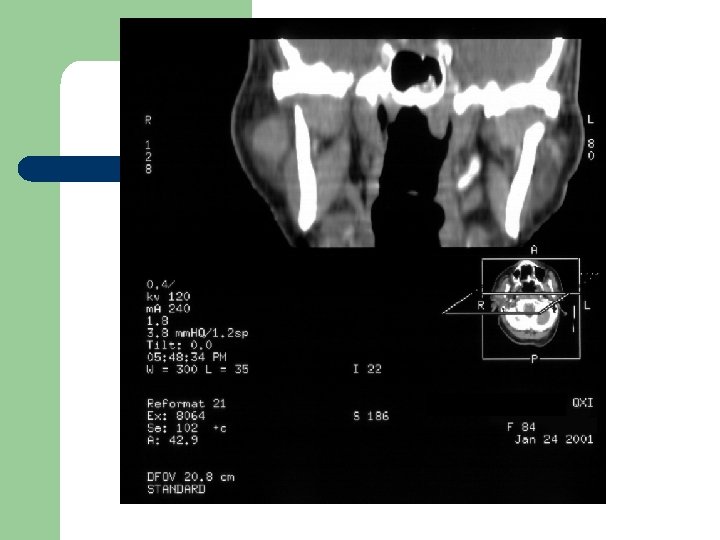

Radiological Evaluation l CT Scan and MRI: To determine the extension of the disease.